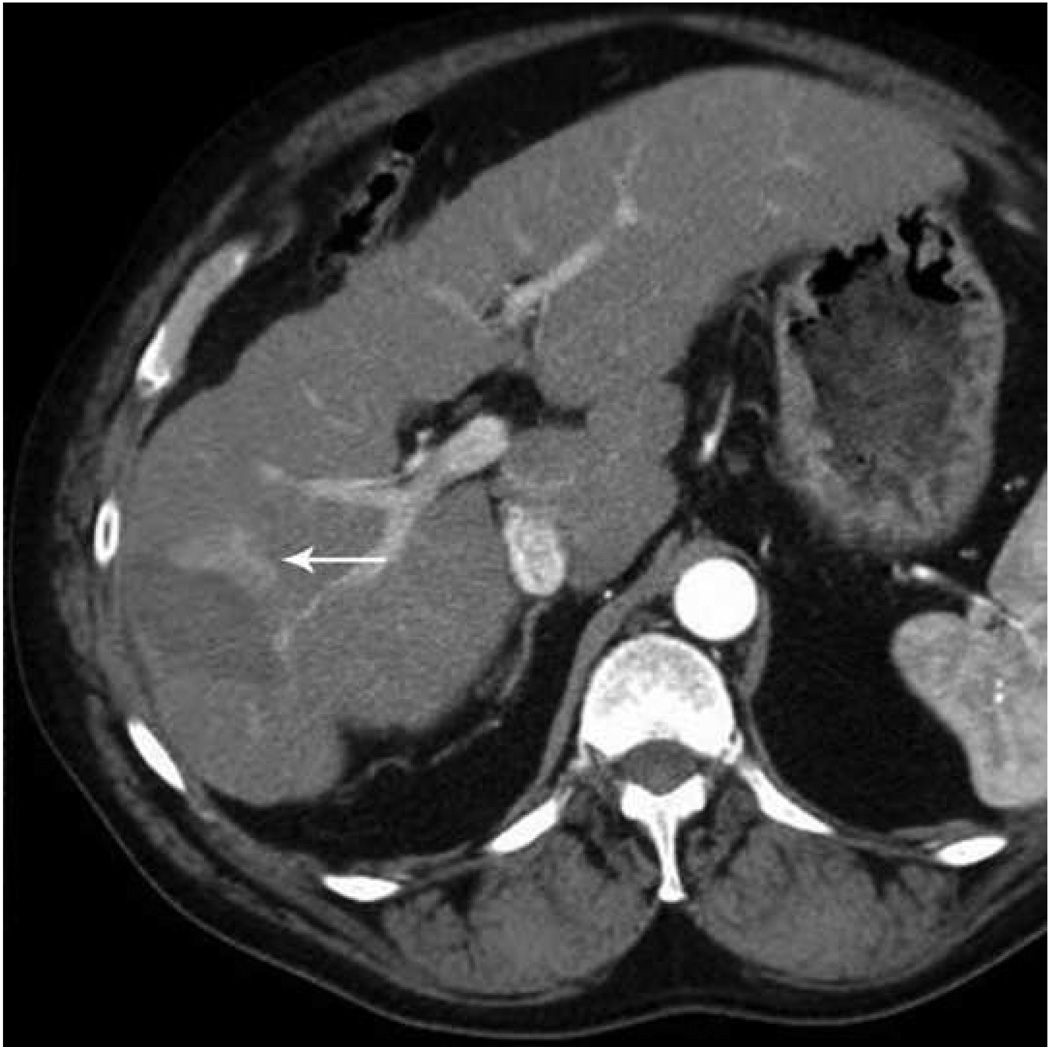

Currently available microwave systems continue to face technical limitations, and this has prevented the potential of microwave from being realized in the clinic to date. Major limitations include underpowered systems, shaft heating, large diameter probes, long and relatively thin ablation zones which have limited clinical application (especially in small bone lesions such as osteoid osteomas and solid organ surface lesions). Similarly, there is still some unpredictability to the size and shape of the zone of ablation which may be related to technical factors (Figures 8, 9)

Figure 8.

Microwave ablation of small hepatocellular carcinoma using the Covidien Evident™ system. Pre ablation CT (a) demonstrates a small hepatocellular carcinoma (arrow) in a patient with hepatitis C and relatively mild cirrhosis. Two probes were placed, and ablation was performed with a large area of gas bubbles forming on the periprocedural US (b). These probes, run at 45 W for 10 minutes, generated a larger than expected ablation zone (large arrow) that extended into the body wall (small white arrow), seen on post procedure CT (c).

Figure 9.

Microwave ablation of liver lesion using Covidien Evident™ system. Pre procedure CT (a) demonstrates a small hepatocellular carcinoma (arrow) in a mildly cirrhotic liver. Two probes (b) were placed into the lesion and run at 45 W for 10 minutes, similar to the case in figure 5. However, a relatively small area of hyperechoic change was identified on the periprocedural US (arrow, b) and the immediate post procedure CT image (arrow, c) demonstrates a much smaller ablation zone with residual tumor seen along the anterior and medial margins at one month follow up (arrow, d). The variation in result between these two cases may be related to increased sensitivity of microwaves to probe placement and phasing.